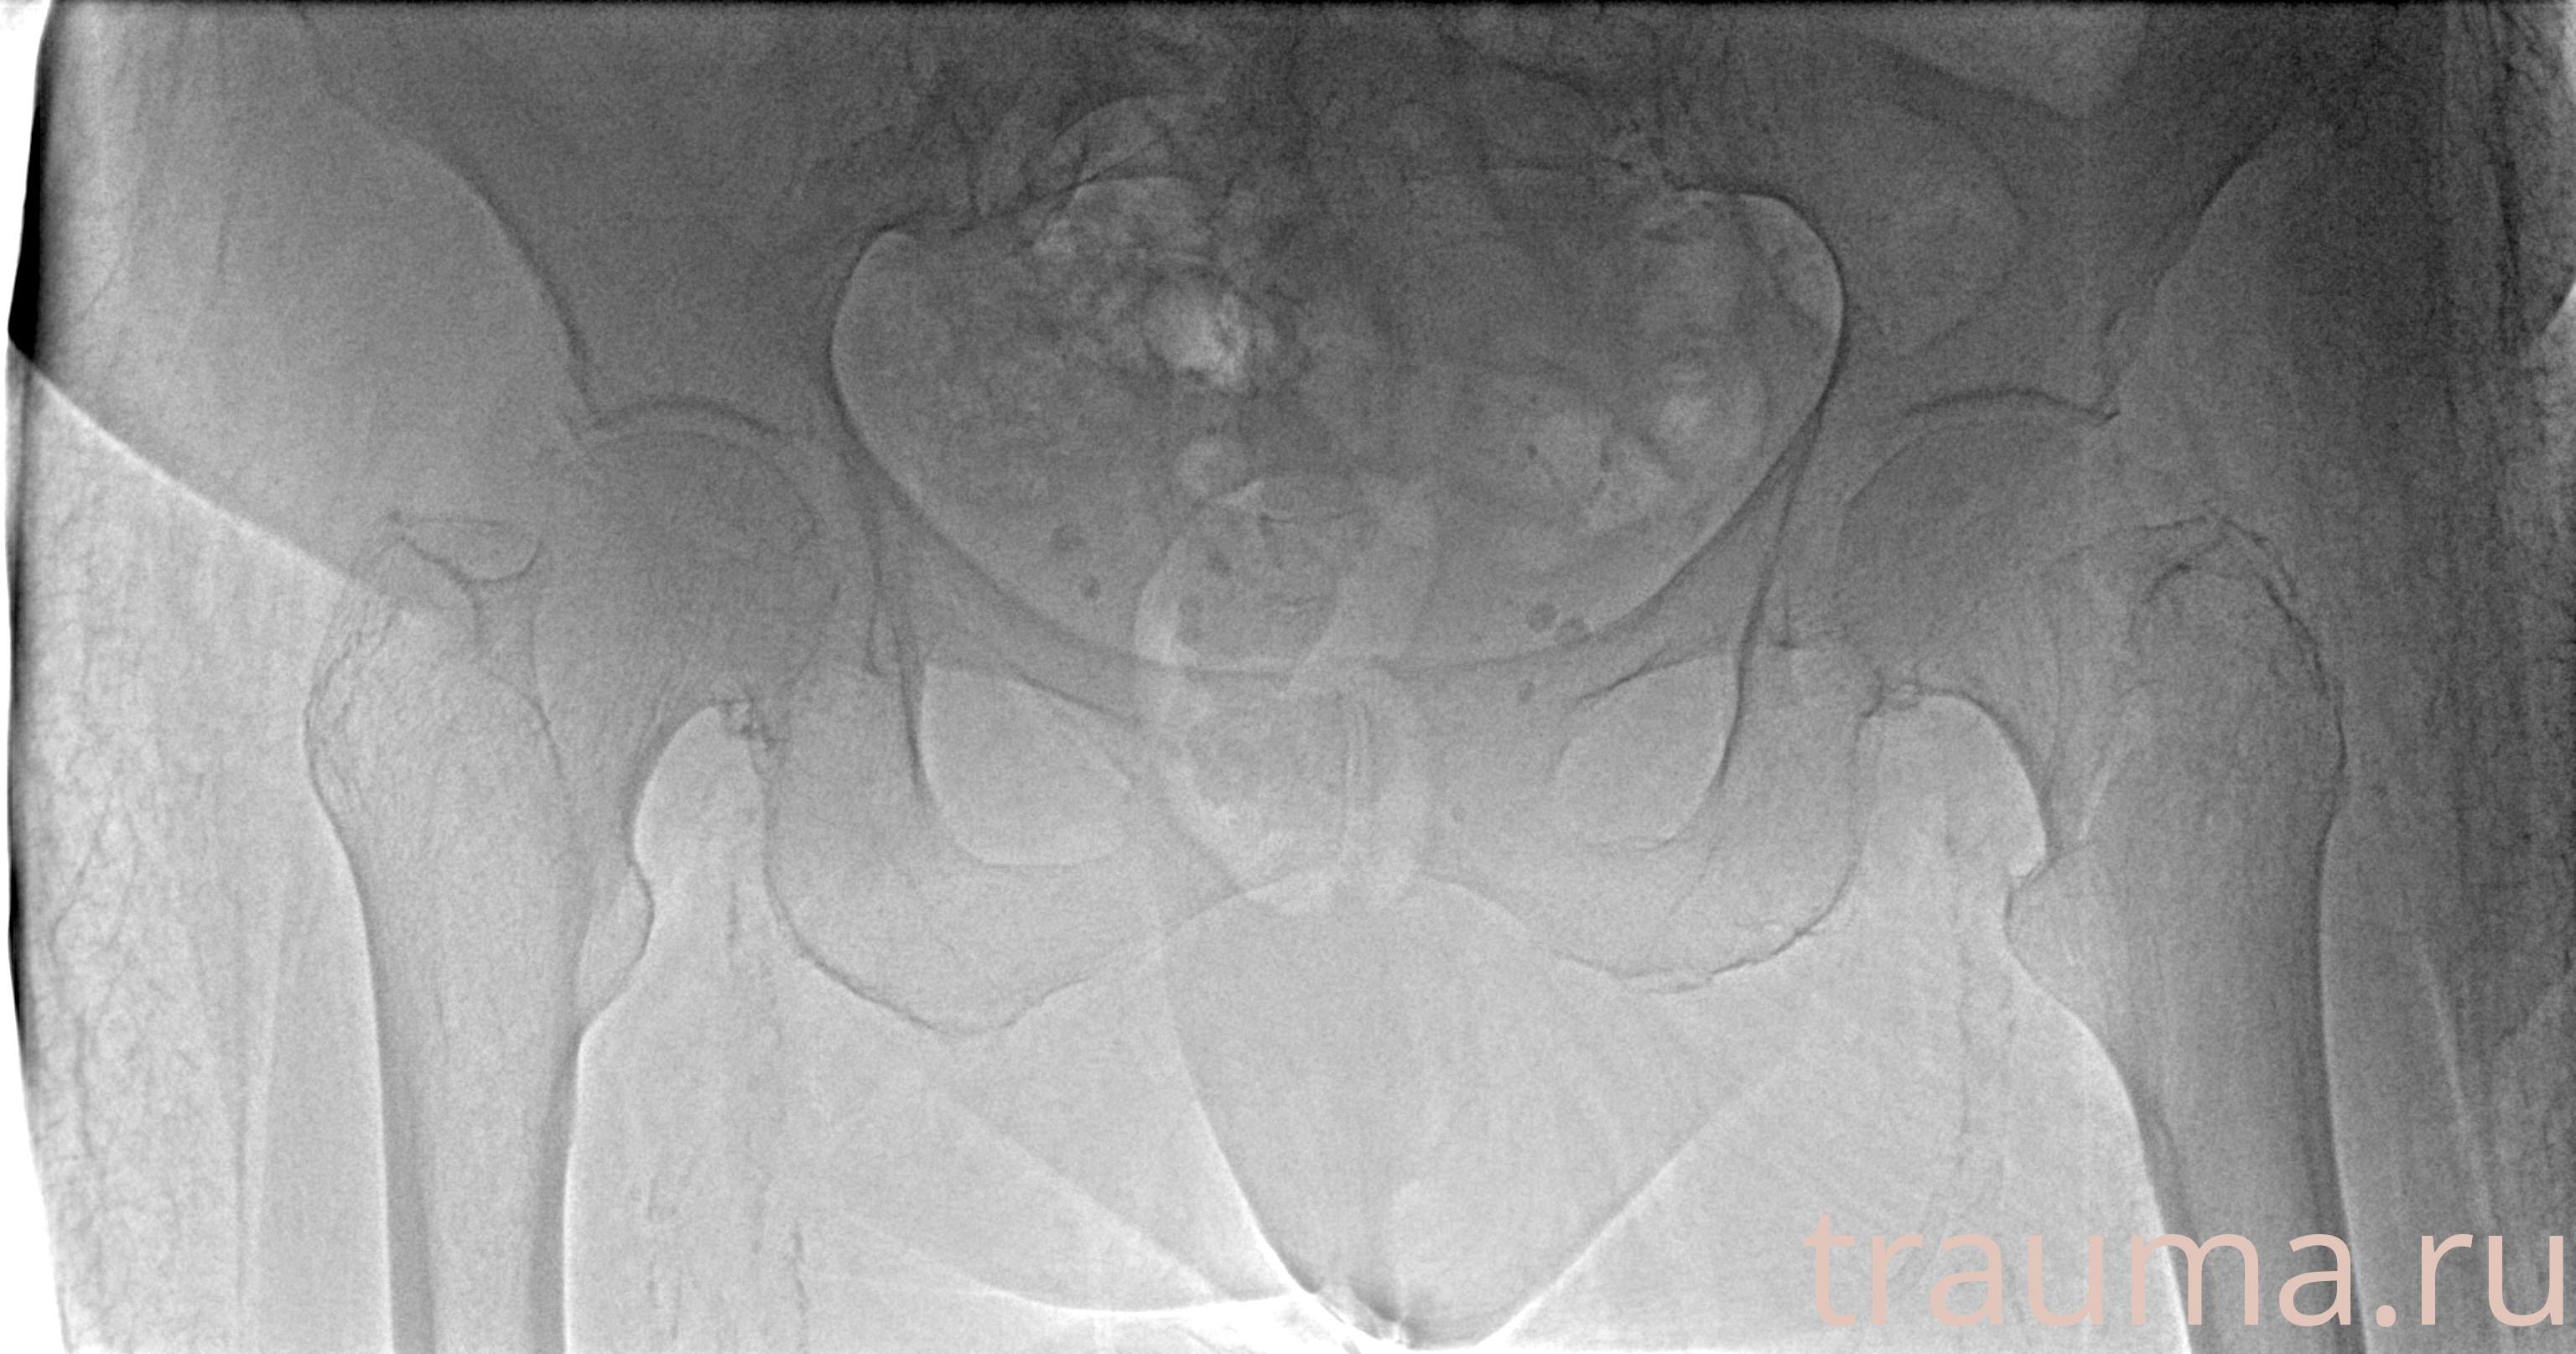

Рентген на дому: по вашему адресу приезжает врач-рентгенолог, травматолог-ортопед с мобильным рентгеновским аппаратом, проводит диагностику травмы или заболевания, делает необходимые рентгенограммы, дает рекомендации по дальнейшему лечению. Получить качественные снимки в домашних условиях возможно благодаря уникальной методике, разработанной МосРентген Центром для института  Склифосовского